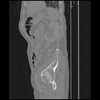

7 CUERPO,CE,Sagittal,3.000,CUERPO,Sagittal,